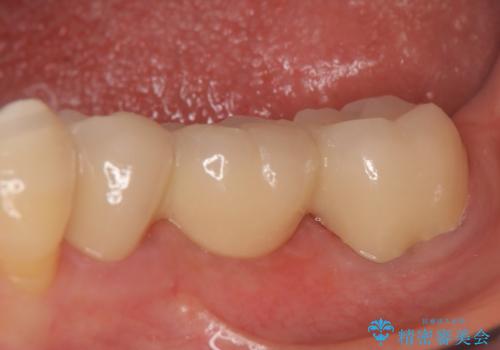

オールセラミッククラウン 欠損補綴と再生療法による深いポケットの改善

骨の定着を待ちポケットが3mm(正常範囲内)であることを確認後、オールセラミッククラウンによる欠損補綴を行いました。

オールセラミッククラウンについて

今回用いたオールセラミッククラウンはジルコニアフレームという白い素材の上にセラミックを盛っているため、審美性が非常に高いのが特徴です。

また、ジルコニアは人工ダイヤモンドの材料にも使われているほど高い強度を持っており、そのためオールセラミッククラウンは審美性だけでなく、奥歯やブリッジの補綴も可能とするクラウンです。